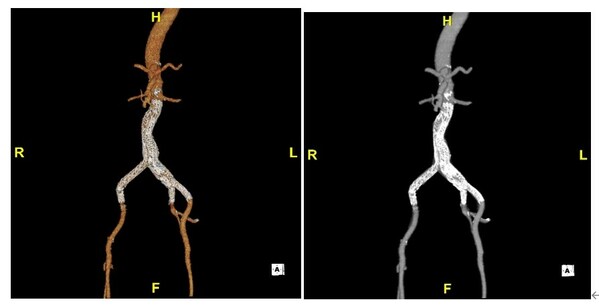

術(shù)后CTA復(fù)查

手術(shù)歷經(jīng)兩小時后順利結(jié)束,手術(shù)創(chuàng)傷小,患者出血少,各方面恢復(fù)良好。